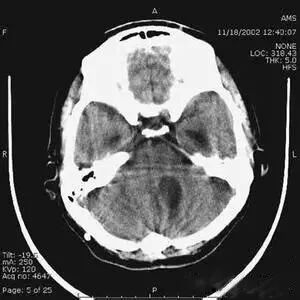

部分容積效應(yīng)偽影的形狀可因物體的不同而不一樣,一般在重建后橫斷面圖像上可見條形、環(huán)形或大片干擾的偽像。最常見和典型的現(xiàn)象是在頭顱橫斷面時的顳部出現(xiàn)的條狀偽影,又稱哼氏偽影。該偽影現(xiàn)象可采用薄層掃描而減弱;在西門子系列的CT機中.用VAR掃描技術(shù)可抑制該偽影。

5、部分容積效應(yīng)產(chǎn)生的偽影及對策